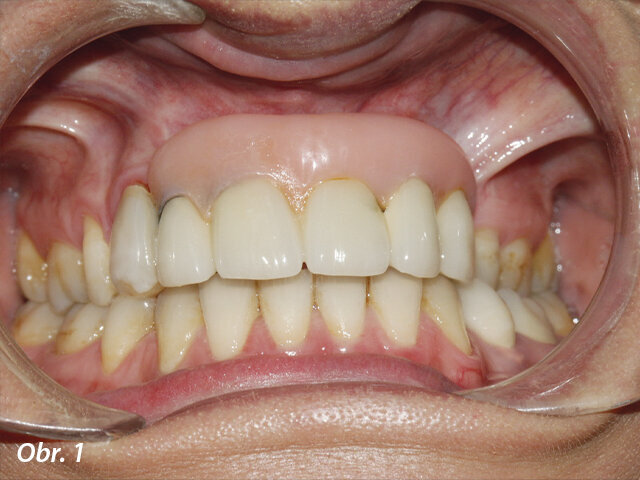

Původní ošetření spočívalo v zavedení dvou implantátů do zbytkové kosti a umístění můstkové konstrukce kotvené šroubky, která měla nést snímatelnou náhradu o rozsahu pěti zubů s rozsáhlou částí umělé gingivy (obr. 1).

Pacientka byla s ošetřením nespokojena a tři roky po prvním ošetření se dostavila na další vyšetření. Úsměv pacientky odhaloval prosvítání konstrukce v oblasti pravého postranního řezáku a protetické zuby byly umístěny mimo středovou linii. Opora rtu zajištěná rozsáhlou umělou gingivou byla v pořádku. U pravého horního špičáku byl odlomený estetický materiál (obr. 1, 2).

Prvotní náhrada: opora rtu byla zajištěna rozsáhlou umělou gingivou a u pravého horního špičáku bylo patrno odlomení estetického materiálu. Úsměv pacientky odhaloval protetické zuby umístěné mimo středovou osu a prosvítání konstrukce u pravého postranního řezáku.